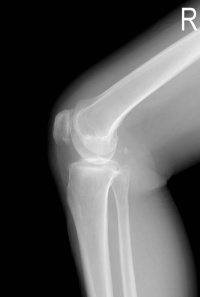

发生率为43%~57%,其中仅55%有关节疼痛症状,检查可见关节病变,有些关节不痛,物理检查也正常者,X线可发现有病变,如囊性变和关节边缘硬化改变,多见于第二、三掌指关节,膝、髋关节也可受累。关节病变发生率与有否肝硬化无关,可作为首发现或唯一表现。

1.X线摄片检查手、腕或其他受累关节显示软组织肿胀。关节间隙狭窄、关节面不整和骨密度减低。骨质疏松及骨皮质囊肿也较常见。软骨钙化和关节周围韧带钙化是关节病的晚期表现。